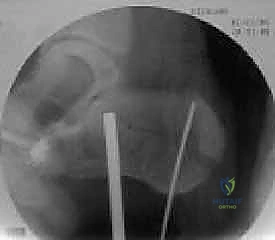

4. التثبيت المؤقت

يتم استخدام أسلاك معدنية دقيقة لتثبيت الشظايا في مكانها مؤقتاً، ثم يتم التحقق من دقة الرد باستخدام جهاز الأشعة السينية داخل غرفة العمليات (C-arm) لضمان عدم وجود أي انزياح ولو بمليمتر واحد.

صور إضافية من داخل غرفة العمليات توضح دقة الإجراء

توضح الصور التالية مدى تعقيد الجراحة والدقة التي يتطلبها تثبيت عظم الكعب، والتي يعكسها التميز الجراحي للأستاذ الدكتور محمد هطيف: